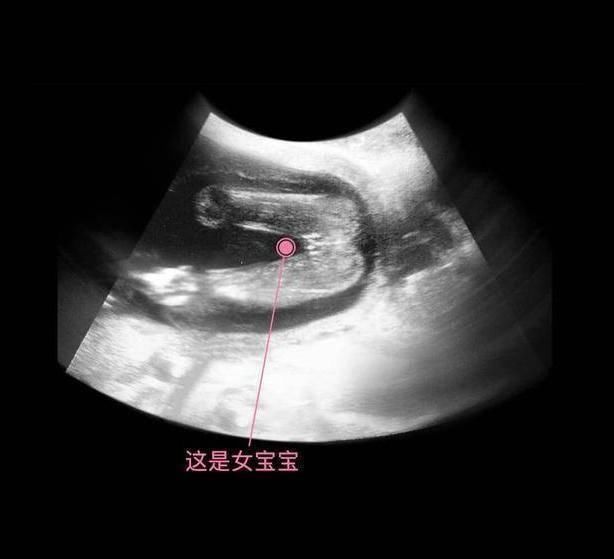

其实从孕9周开始,胎儿的性别就开始分化,孕17周,B超扫描清晰可见胎儿的性别,不过也有的宝宝因为胎位的原因,或者脐带遮挡,让医生产生了误判,男女会出现翻盘的可能呢。